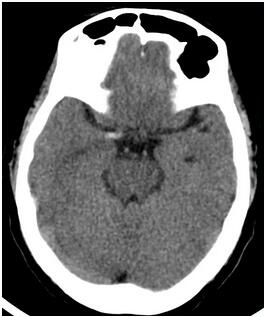

到达医院后,检查头颅CT影像,发现在右侧大脑中动脉处存在高密度影,考虑右侧大脑中动脉M1段出现栓塞。从晚上八点开始发病,到考虑是脑栓塞已经过了两个小时了。

手术过了五天,神经内一科为王阿姨复查CT影像。可以看出,相比较手术前,右侧大脑中动脉的高密度影已经明显减轻了。